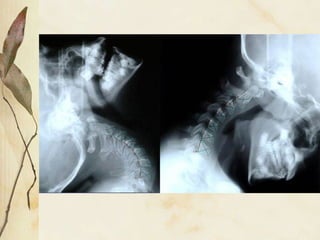

Relação Craniocervical Relação entre occipital, atlas e axis 50% da função cervical ocorre a este nível Espaço C0-C1-C2, pode ser diminuído por rotação posterior de crânio ou por inclinação cervical

Relação Craniocervical Relaçãoentre occipital, atlas e axis 50% da função cervical ocorre a este nível Espaço C0-C1-C2, pode ser diminuído por rotação posterior de crânio ou por inclinação cervical